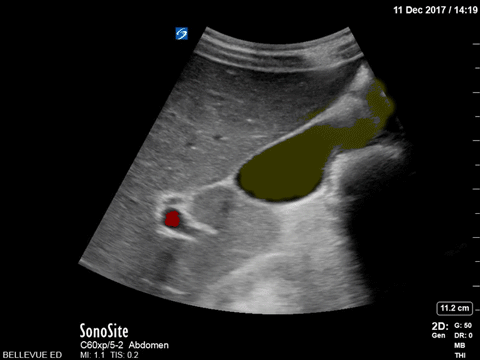

Normal Gallbladder Yellow: Lumen of gallbladder, Red: Portal vein, Green: Common bile duct Images: Dr. Lindsay Davis, Dr. Hannah Kopinski. Image Editing: Michael Amador and Dr. Matthew Riscinti